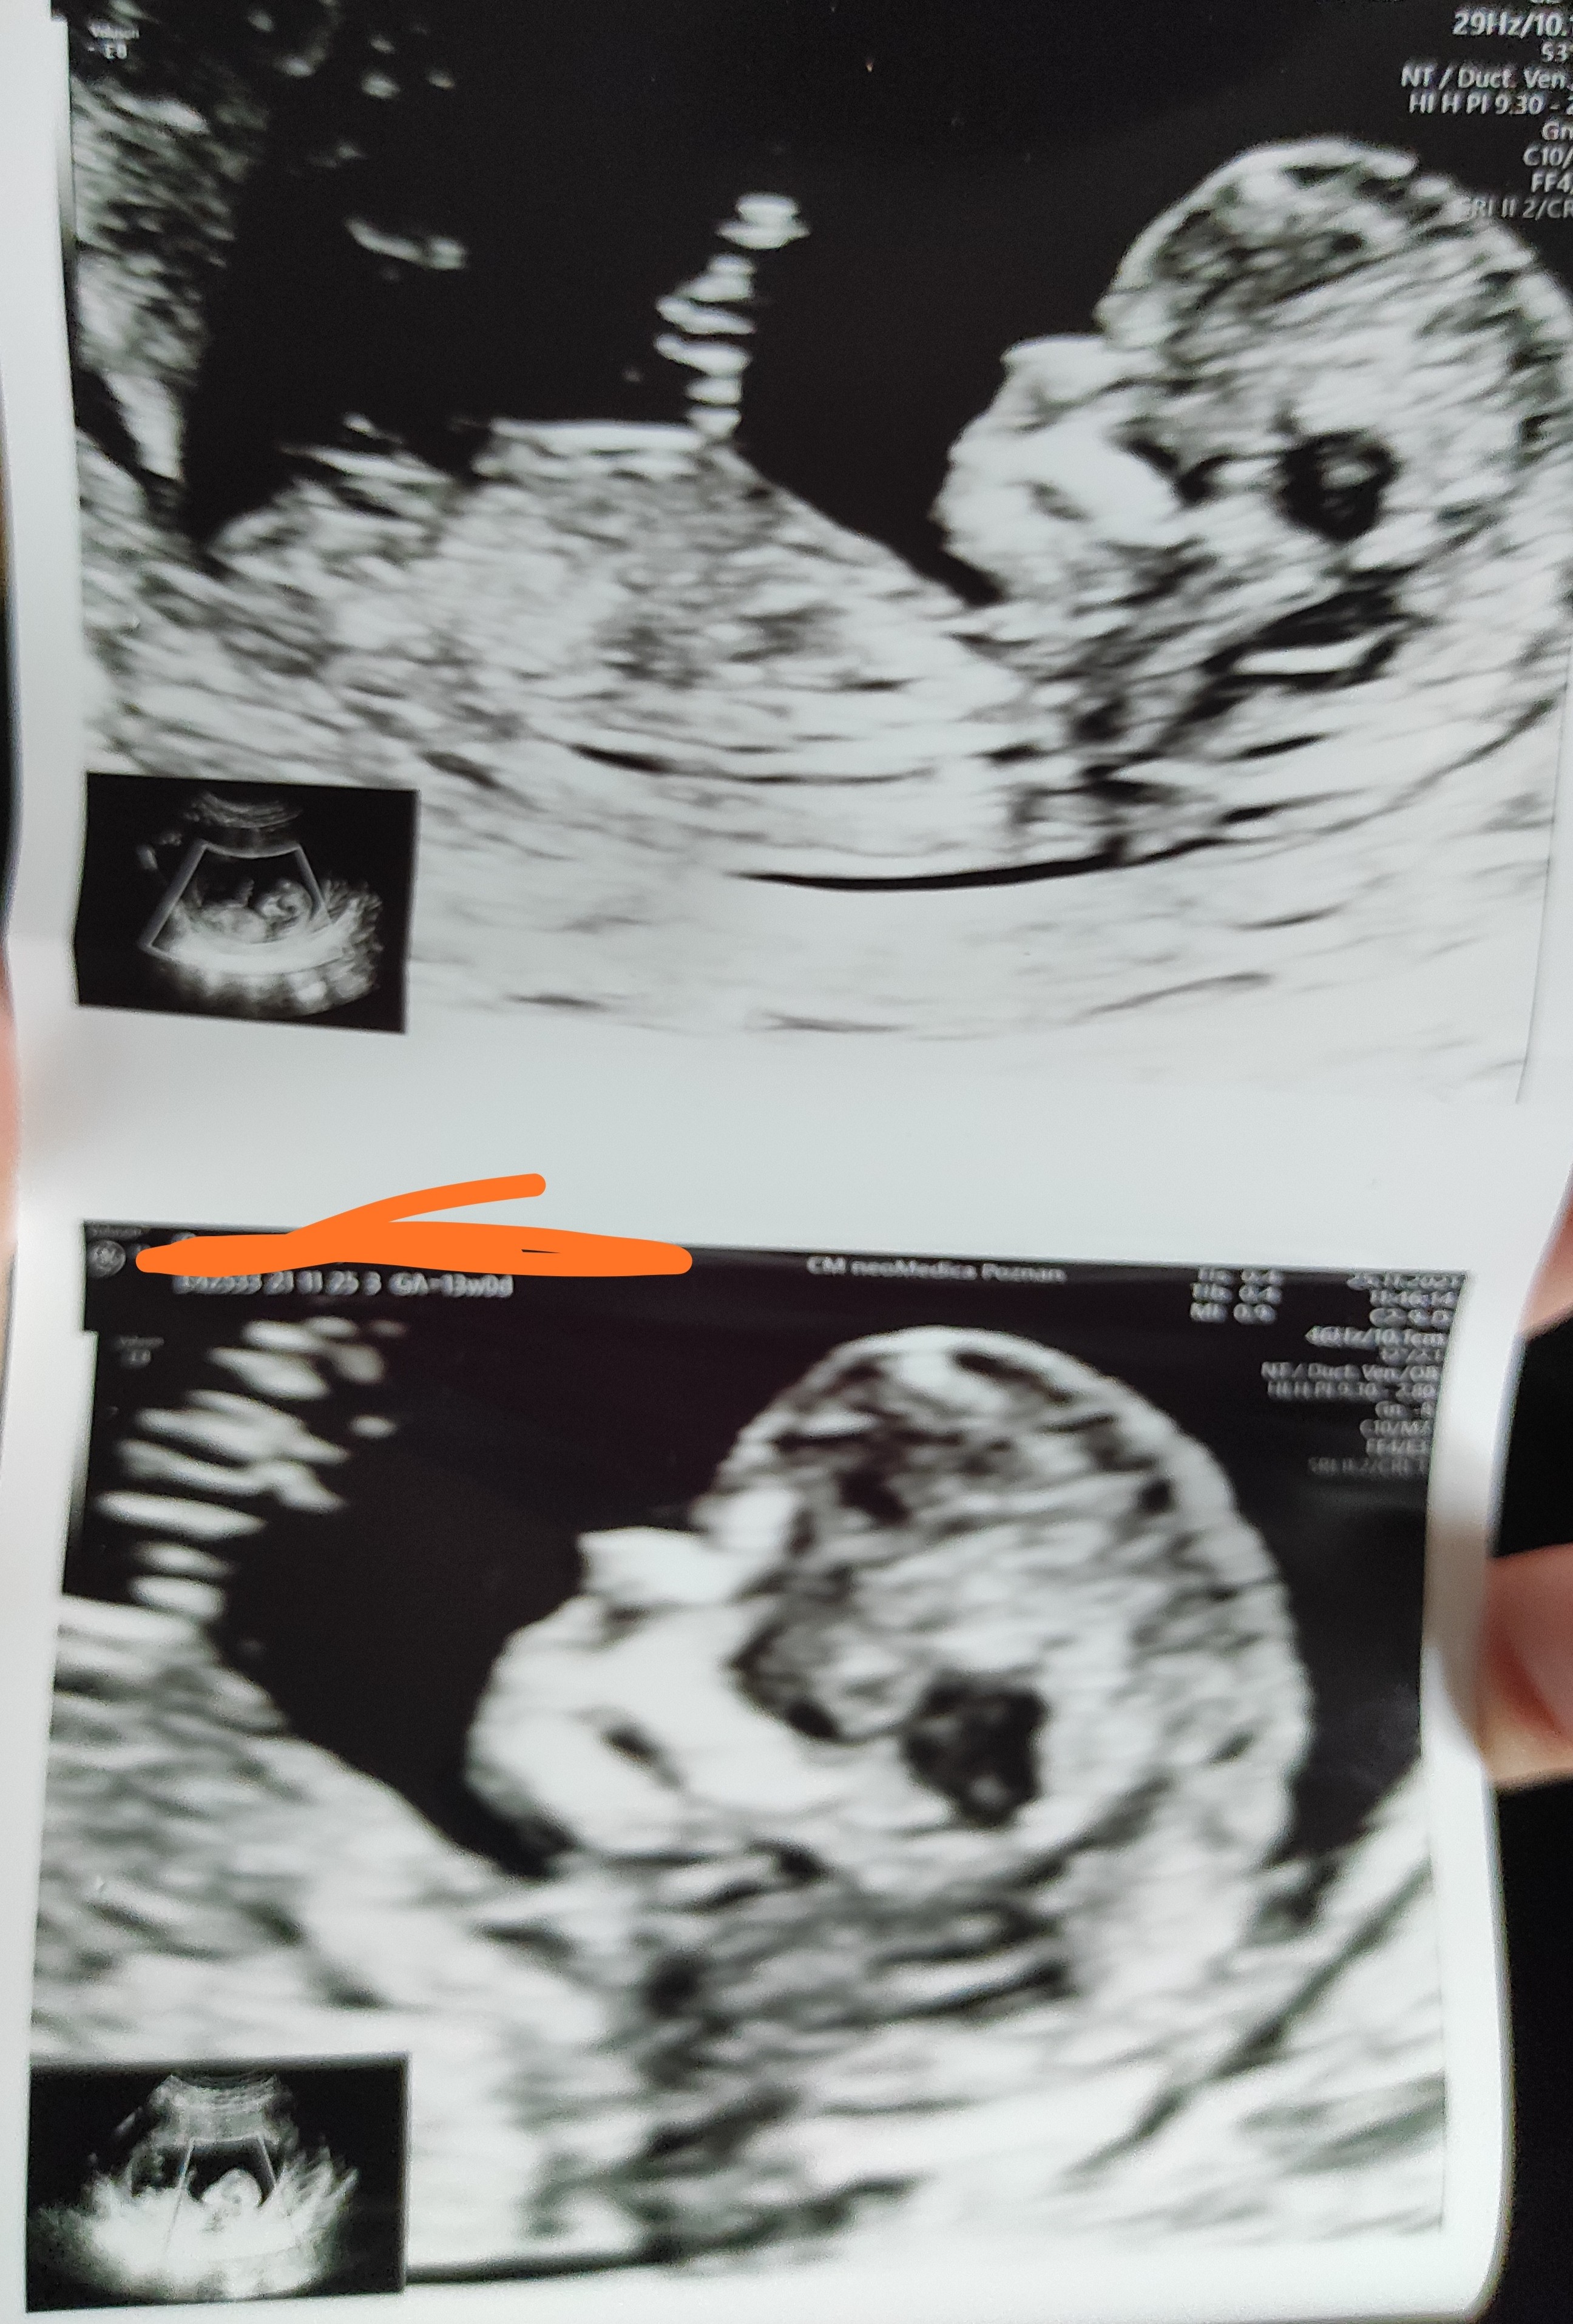

Ja już po prenatalnych (@PsychoPatka91 usuń proszę jutrzejszą wizytę i przełóż na 17.12).

Dzidziuś zdrowiutki ❤️ Od razu pobrano mi krew na Pappę i w ciągu dwóch tygodni mam mieć opis od pani doktor. Ale z tego co widziała na USG, to nie powinno nic wyjść. Kłuli mnie oczywiście trzy razy, ale nadal poniżej rekordu 😂

Na początku nie chciała określić płci, bo powiedziała, że nie lubi się mylić (była bardzo dokładna w swoim badaniu), ale na końcu stwierdziła, że na 80% chłopak, więc moja intuicja, objawy i babcine zabobony mają rację 😂

Dzidziut w załączniku ❤️